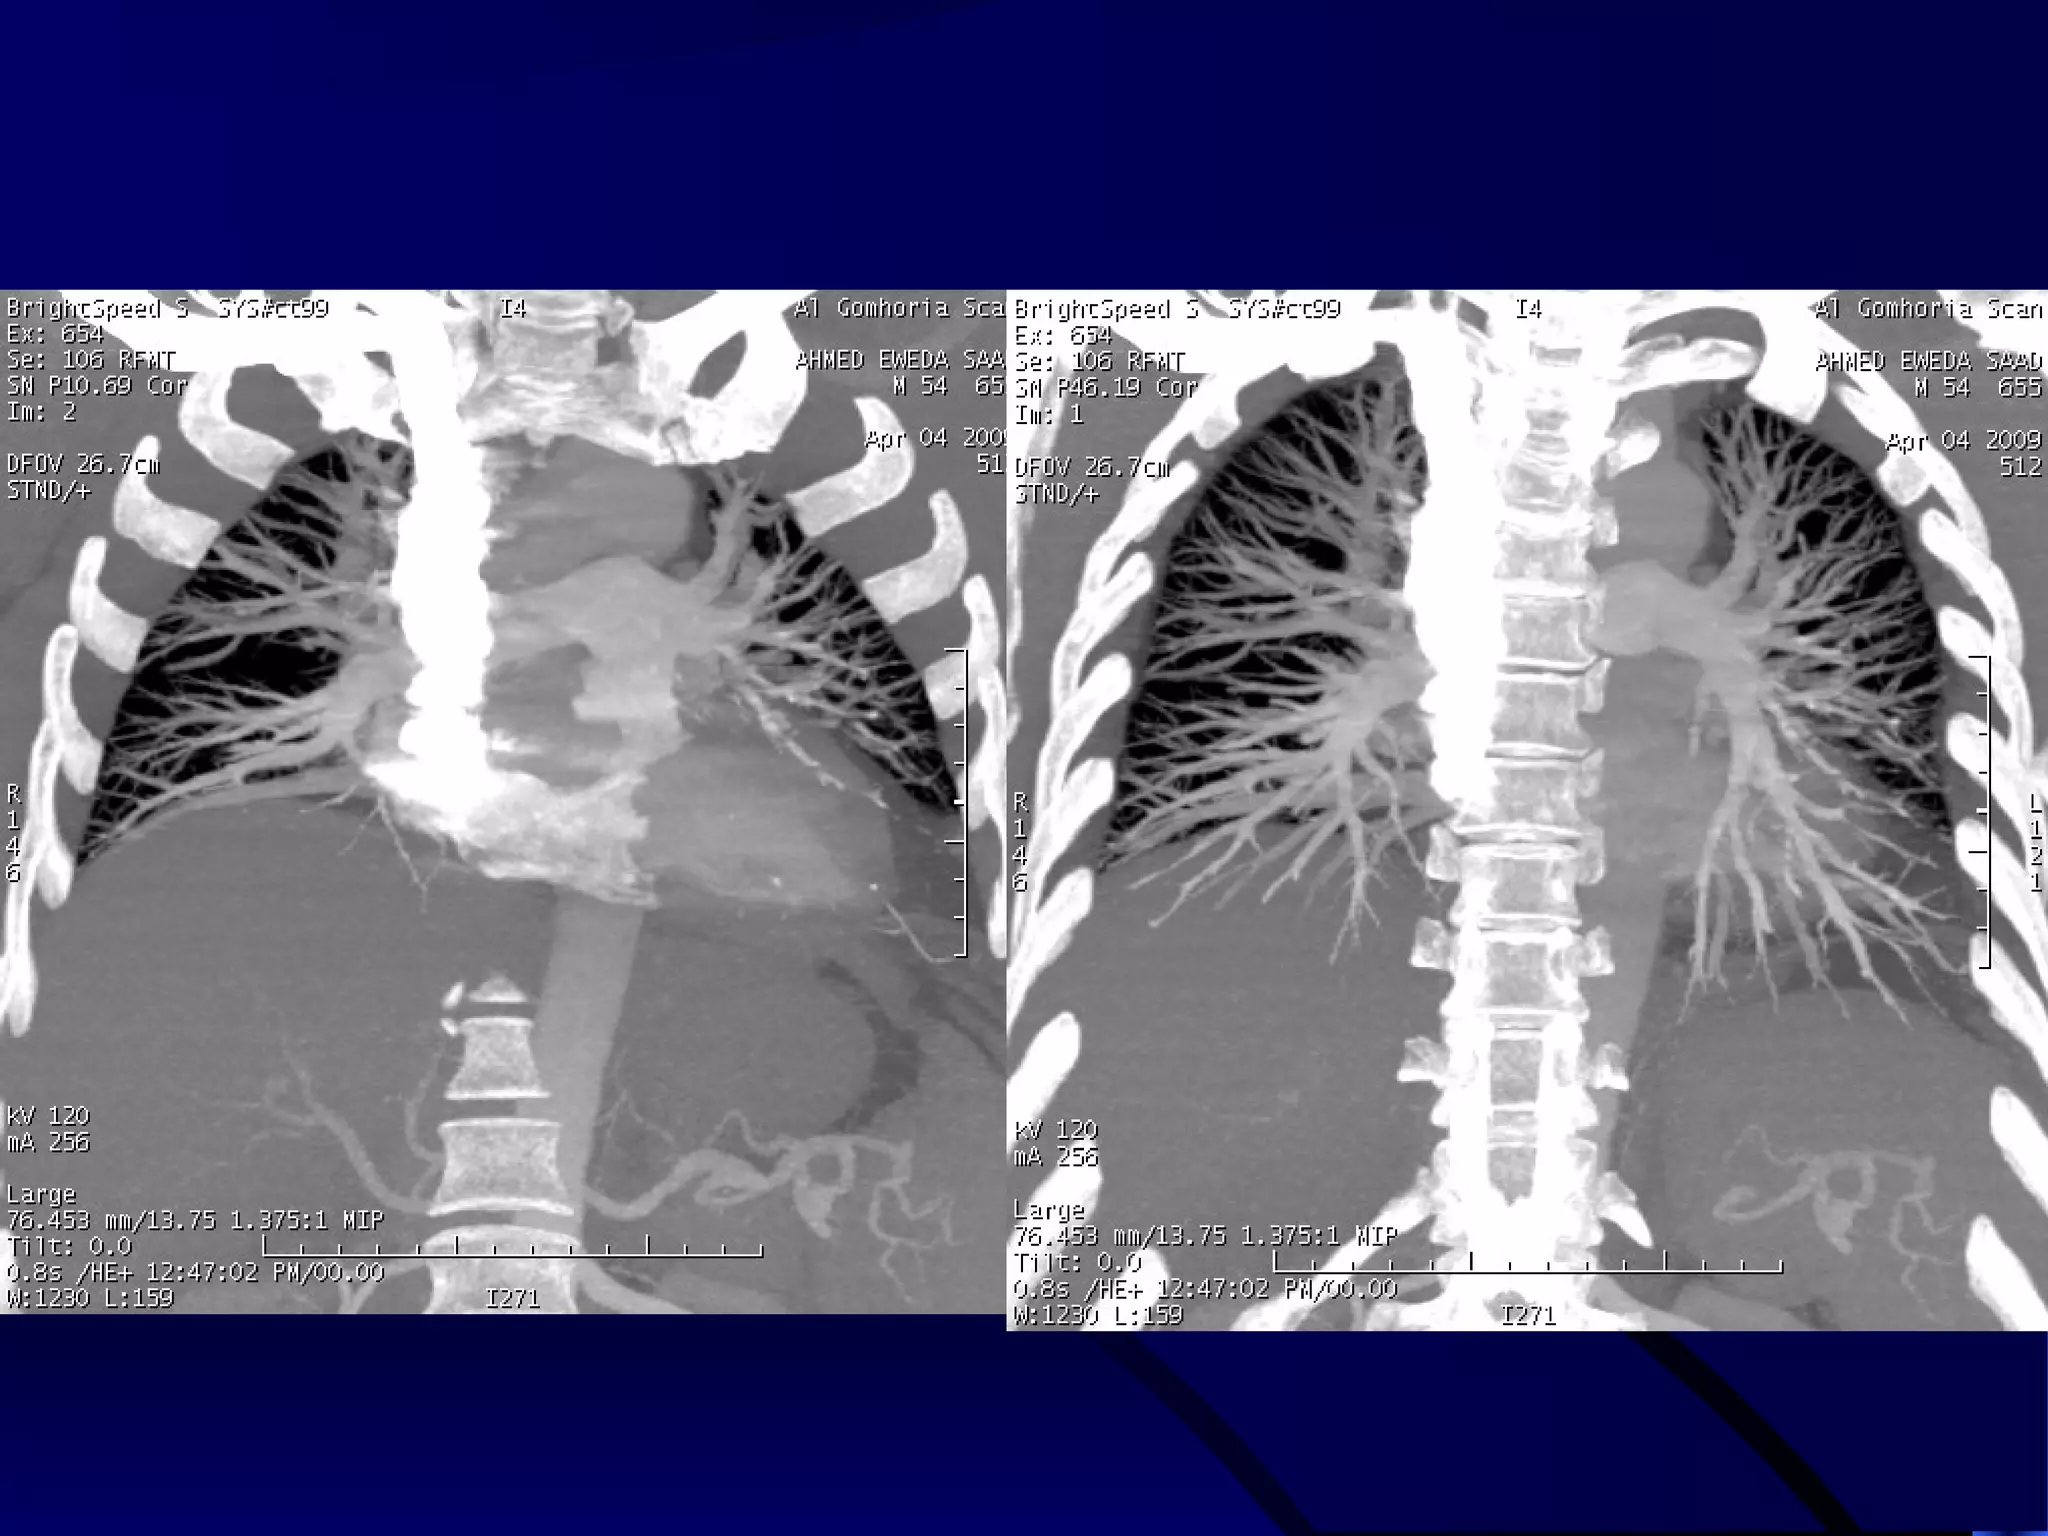

MDCT ANGIOGRAPHY

PULMONARY ARTERIES

MIP IMAGE (POSTERIOR VIEW) VR DOUBLE DENSITY IMAGE

(POSTERIOR VIEW)